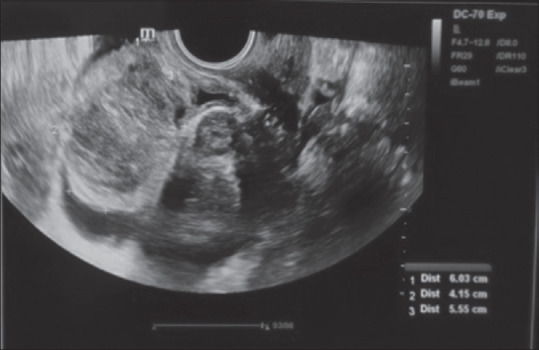

Owing to its simplicity, transvaginal oocyte retrieval (TVOR) has become the standard procedure for oocyte retrieval. Despite being an easy procedure, TVOR is still associated with rare but serious complications. A high index of suspicion is required for early diagnosis of complications. We present two cases of bladder haematoma, which presented to us post-TVOR.